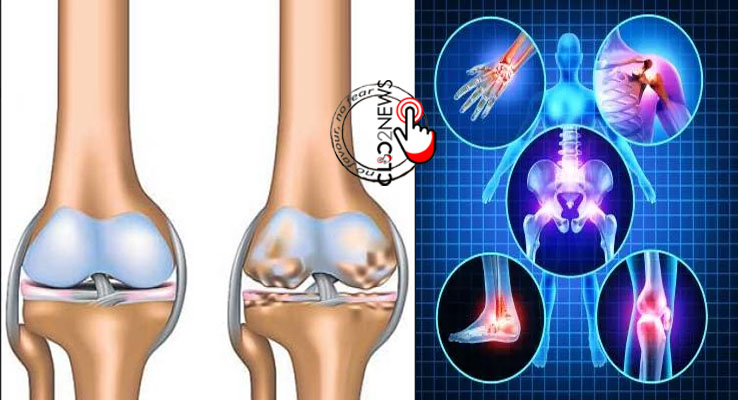

సంధివాతం.. (అస్టియోఅర్ధరైటీస్ ) వయసు పెరుగుతున్న కొద్ది కీళ్ళ నొప్పులు వస్తుంటాయి. కానీ ఈ సమస్య స్త్రీలలో ఎక్కువగా ఉంటుంది. కొందరికి వయసుతో సంబంధం లేకుండా కూడా ఈ లక్షణాలు కనబడుతున్నాయి. కానీ ఇప్పుడు మాత్రం దీనికి కొద్దిగా విరుద్ధంగానే వుంది. తినే ఆహారంలో చక్కని పోషక పదార్ధాలు అందకపోవటం, ప్రకృతికి విరుద్ధంగా ఆహారం తీసుకోవటం, సరైన వ్యాయామం లేకపోవటం, అధిక వ్యాయామం చేయటం, మోకాళ్ళ కీళ్ళు, తుంటి కీళ్ళు, నడుము కీళ్ళు దగ్గర మెడ దగ్గర కీళ్ళు దగ్గర నొప్పులు రావటం జరుగుతుంది. ముఖ్య కారణం కీళ్లలో వున్న కార్టీలేజ్ దెబ్బతినటం వలన ఎముకలు గరుకుగా మారటం ఎముకల మధ్య ఖాళీ ప్రదేశంలో లేకపోవటం, కదిలినపుడు ఎముకలు గరగర గా అనటం జరుగుతుంది. ఎముకల దగ్గర వున్న కండరాల లిగమెంట్స్ బిగసుకుంటాయి.కీళ్ళు పరస్పరం రాసుకుంటాయి. నొప్పులు వస్తాయి. వాపులు వస్తాయి. జాయింట్లు పెళలుసు మారి విరిగిపోతాయి. దీనినే సంధివాతం అంటారు. భారతదేశంలో ఏటా పది కోట్ల మందికి పైగా ఈ జబ్బుతో బాధపడుతున్నారు.

లక్షణాలు.

1. కీళ్ళు బాగా నొప్పి రావటం.

2. పట్టుపట్టటం.

3.రక్తనాళాలు, కండరాలు బలహీనంగా మారటం.

4.కీళ్ళ వాపు, కీళ్ళు వంకర టీంకరగా మారటం,

5.నడవటం, మెట్లు ఎక్కటం ఇబ్బందిగా ఉండటం.

6.కాళ్ళు చాచాలన్న,మడవ లన్న, చాలా ఇబ్బంది పడటం,

7.నొప్పితో కీళ్లలో నీరు చేరటం జరుగుతుంది.

8. దూరంగా నడిచినపుడు గర గర శబ్దం రావటం జరుగుతుంది.